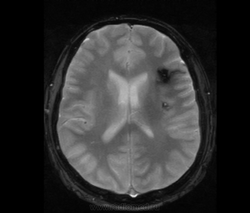

М, 27 лет. Жалобы на головные боли. ЧМТ в анамнезе. Стационар выставил внутримозговую гематому по КТ, полечили, отпустили.  К нам пришел на контроль.

Локализация таламус, граница коркового/мозгового, похоже на множественные кавернозные ангиомы. То, что в левой лобной?

Хочу посоветоваться с коллегами).  Дифференциальный ряд построить. Например токсоплазмоз, метастазы....в общем жду.

Сложно представить у молодого человека и каверномы, и метастазы одновременно.

Наверное, все же множественные каверномы, слева -осложненная кровоизлиянием.

Пришел к выводу, что сдесь все таки не каврномы, а мелкоочаговые кровоизлияния (ДАП). Учитывая травму и пребывание после этого  пациента в коме.